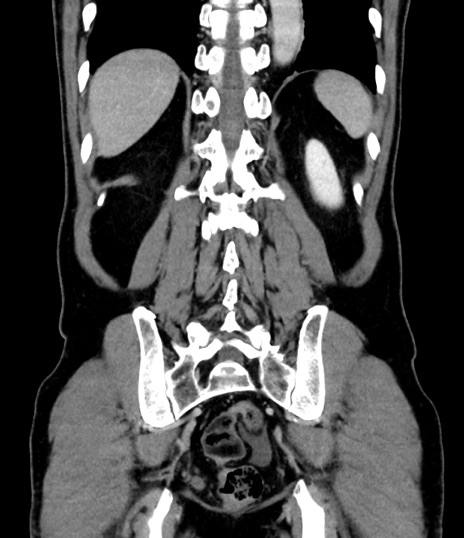

症例8(冠状断像)

【症例】 60歳代男性

【主訴】 黒色吐物

【現病歴】 4日前から嘔気自覚、2日前の朝食後にも嘔気あり、自分で手で嘔吐反射起こし嘔吐したところ血が混ざっていたため受診。

【既往歴】 5年前汎発性腹膜炎を伴う急性虫垂炎で手術、高血圧、前立腺肥大症、高脂血症

【身体所見】 腹部正中に手術癩痕あり 腹部平坦・軟圧痛なし膨満感あり

【データ】WBC 8400、CRP 4.54